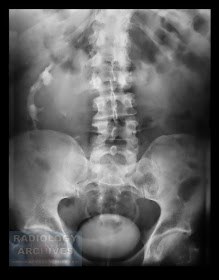

Διασταυρούμενη Εκτοπία Νεφρών

Cross-Fused Renal Ectopia